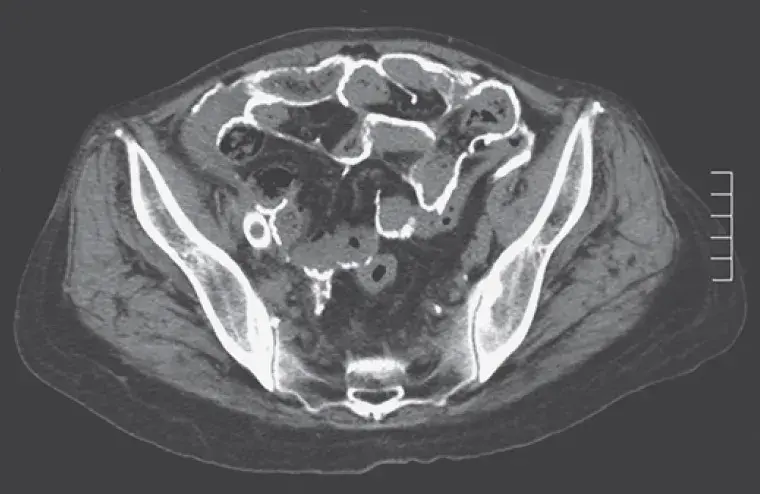

Realizado **TC de abdome** mostrou extensa calcificação do peritônio visceral e parietal (imagem A). Devido forte suspeita de **peritonite esclerosante encapsulante** foi realizado laparoscopia exploratória para confirmação diagnóstica. Pode-se observar um peritônio parietal muito espessado coberto por depósitos calcificados (imagem B). Aderências entre o peritônio e serosas inflamadas podem ser observadas.

- Devemos ter elevada suspeita clínica diante de queixas abdominais, TC de abdome com calcificações peritoneais sugere o diagnóstico.